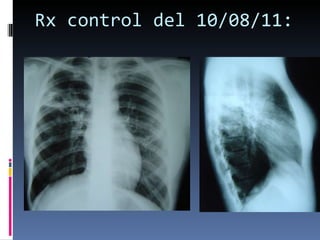

Rx control del 10/08/11:

Rx control del10/08/11: